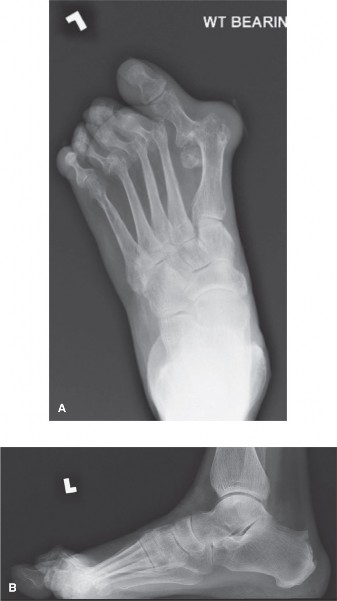

A 54-year-old male presents with right forefoot pain, swelling, and a sense of pressure. He reports that he w…